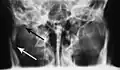

multiple mandible fractures of a patient in the right condyle (extracapsular/neck/not dislocated), right body (vertically unfavourable) and left coronoid process